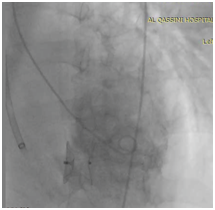

Patient was thrombolysed properly, intubated and sedated and taken to cath lab for urgent PTCA. Echocardiography also showed severe LV systolic dysfunction, a kinetic mid and apical portions, large ventricular septal defect VSD sized 1.3 cm in the form of an oblique tunnel with significant left to right shunt (Figure 1).